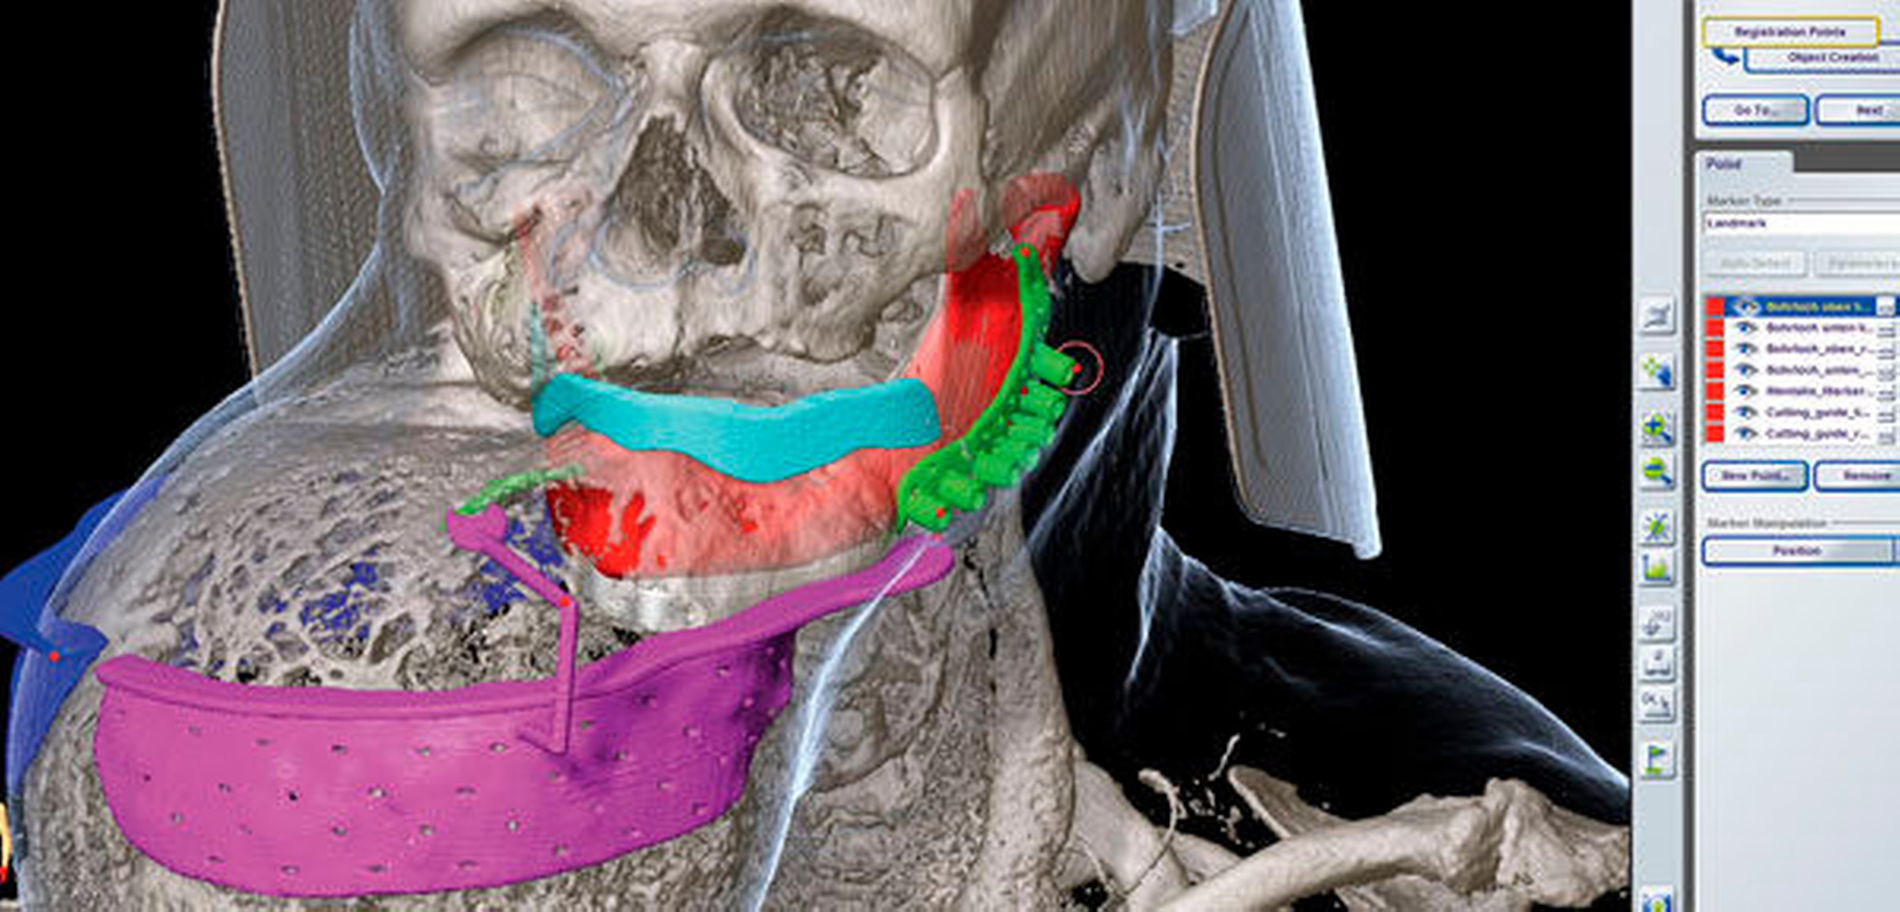

Klinisch zeigte sich eine circa 30 cm x 28 cm x 15 cm große, knochenharte und den Unterkiefer zu drei Vierteln umgreifende Raumforderung ohne Vincent-Symptomatik (Abbildung 1). In der Computertomografie zeigte sich eine inhomogene, blasige und hypodense Raumforderung mit Milchglasanteilen (Abbildung 2). Geplant wurde eine Abtragung der Veränderung mit Rekonturierung des Unterkiefers unter Verwendung eines statistischen 3-D-Formmodells, mit dessen Hilfe die ursprüngliche Form des Unterkiefers ermittelt wurde (Abbildung 3a). Im CAD/CAM-Verfahren wurden vier Resektionsschablonen hergestellt, um die geplante Osteotomie intraoperativ umzusetzen (Abbildung 3b).

Über eine submandibuläre Schnittführung konnte die stark durchblutete Raumforderung vollständig dargestellt werden. Zur Erhaltung der Sensibilität der Unterlippe wurde eine Resektionsschablone mit einem Pointer versehen, um das stark verlagerte Foramen mentale rechts darstellen zu können (Abbildung 4). Intraoperativ zeigte der Unterkiefer eine ausreichende Stabilität, sodass auf eine patienten-individuell hergestellte Rekonstruktionsplatte verzichtet werden konnte (Abbildung 5). Das überschüssige Weichgewebe wurde reseziert und die Wunde plastisch verschlossen.

Im Fall ausgedehnter Befunde kann die Computer-assistierte Chirurgie (Computer-assisted surgery, CAS) auf Basis einer präzisen präoperativen 3-D-Planung helfen, die modellierende Osteotomie vorhersagbar durchzuführen. Als virtuelle Planungshilfe bei einseitigen Befunden ist das etablierte Verfahren die Spiegelung, bei der die gesunde Seite auf die betroffene Seite gespiegelt werden kann [Bittermann et al., 2014; Schmelzeisen et al., 2004]. Bei bilateralen Befunden muss ein komplexeres Verfahren Anwendung finden, bei dem mithilfe eines statischen Formenmodells patientenspezifisch die ursprüngliche Form berechnet wird [Fuessinger et al., 2017; Semper-Hogg et al., 2016].

Im vorliegenden Fall konnte durch diese Technik der ursprüngliche, nicht deformierte Unterkiefer errechnet werden. Anhand dieser Oberflächenabschätzung wurden insgesamt vier patientenspezifische Resektionsschablonen erstellt um die präoperative Planung intraoperativ präzise und schnell umsetzen und anatomisch sensible Strukturen, wie den N. mentalis, mithilfe von Pointern schützen zu können.